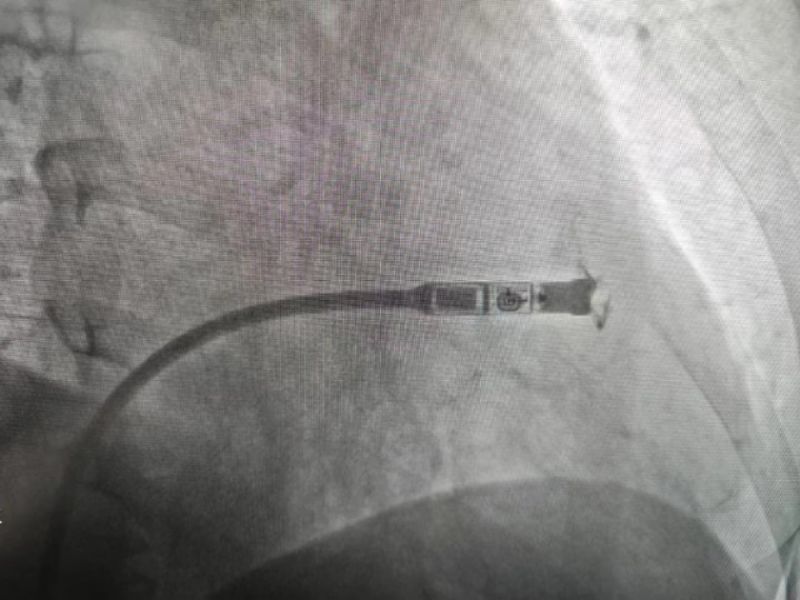

手术过程:经过充分的术前讨论,在延安大学咸阳医院心血管病院吴栋梁院长、刘雄涛副院长的指导与支持下,李阳教授、何克强主治医师、辛浩主治医师与导管室介入团队的共同努力下,经过超声科、心电中心等多学科协作,成功为患者植入双腔无导线永久起搏器,术后第二天患者在起搏器保障下经药物治疗恢复正常的窦性心律。目前患者心脏情况及脑梗均恢复良好,已顺利出院。

科普:Micra无导线起搏器号称“世界最小起搏器”,无需植入心内膜导线,也无需在胸前皮下制作囊袋放置脉冲发生器(起搏器),手术仅需局部麻醉,通过股静脉穿刺,将起搏器经导管植入心腔内,手术时间短,减少出血、血肿及感染风险,术后恢复快,肢体活动不受限,无异物感。

优势:比传统起搏器体积减少93%,体积更小,重量仅2g,类似一颗维生素胶囊;虽体积只有传统起搏器十分之一,但其小小身体储存大能量,续航时间超过12年,整个手术过程平均约30分钟,植入成功率高,术后8-12小时即可下床活动,术后1-2天即可出院;兼容1.5T(特斯拉)/3.0T全身核磁共振扫描。满足患者植入Micra之后疾病的诊断和治疗需求。